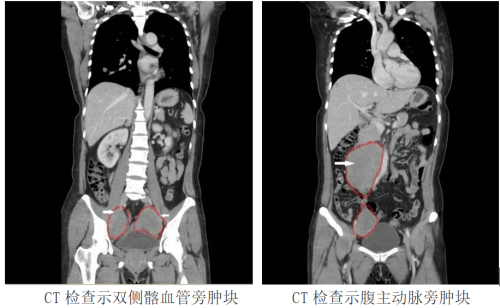

带着满心的困惑和担忧,罗研入住到了妇产科三区。科室主任魏馨仔细查看后,认为患者盆腹腔多个实性包块,性质来源不明,有手术指征,建议行开腹探查术,彻底切除病灶。在得到患者及家属的同意后,魏馨带领团队为患者进行了开腹盆腔巨大肿物切除术+双侧输卵管卵巢切除术+宫颈切除术,术中证实,患者腹中确实再次长出了肌瘤,且分布广泛,在盆腔两侧腹膜后紧贴髂血管处,以及腹主动脉旁均可见肌瘤样肿物,最大的直径达12cm。因肿瘤均紧邻血管,稍有不慎就可能损伤大血管,导致大出血,手术难度极高。经过紧张有序的手术,肌瘤被一一切除,术中病理检查提示肿物为良性平滑肌瘤。术后5天,罗研康复出院。